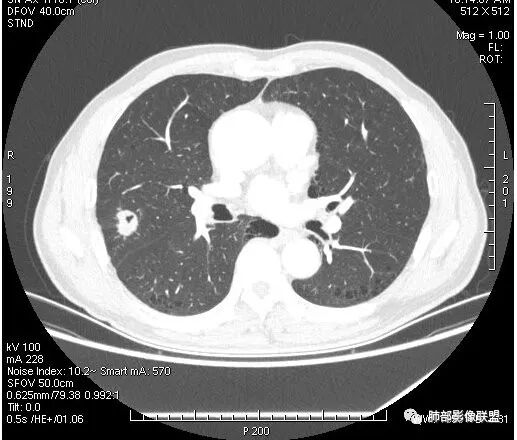

影像学改变:

1.右肺上叶后段类圆形结节影,密度不均,有坏死空洞,坏死比较彻底,内外壁都较清楚。

2.病灶有浅切迹,没有深分叶,毛刺大多细长且柔软。

3.可见棘状突起及胸膜牵拉,但未见胸膜凹陷。

什么意思?结节影有牵拉的动作,但似乎“出工不出力”,收缩力羸弱!

4.病灶轻到中度强化。病灶内血管走行较完好,病灶旁血管局部显示粗大。

5.支气管关系不确定。

6.灶周见小结节影(卫星灶),边界不甚清晰。